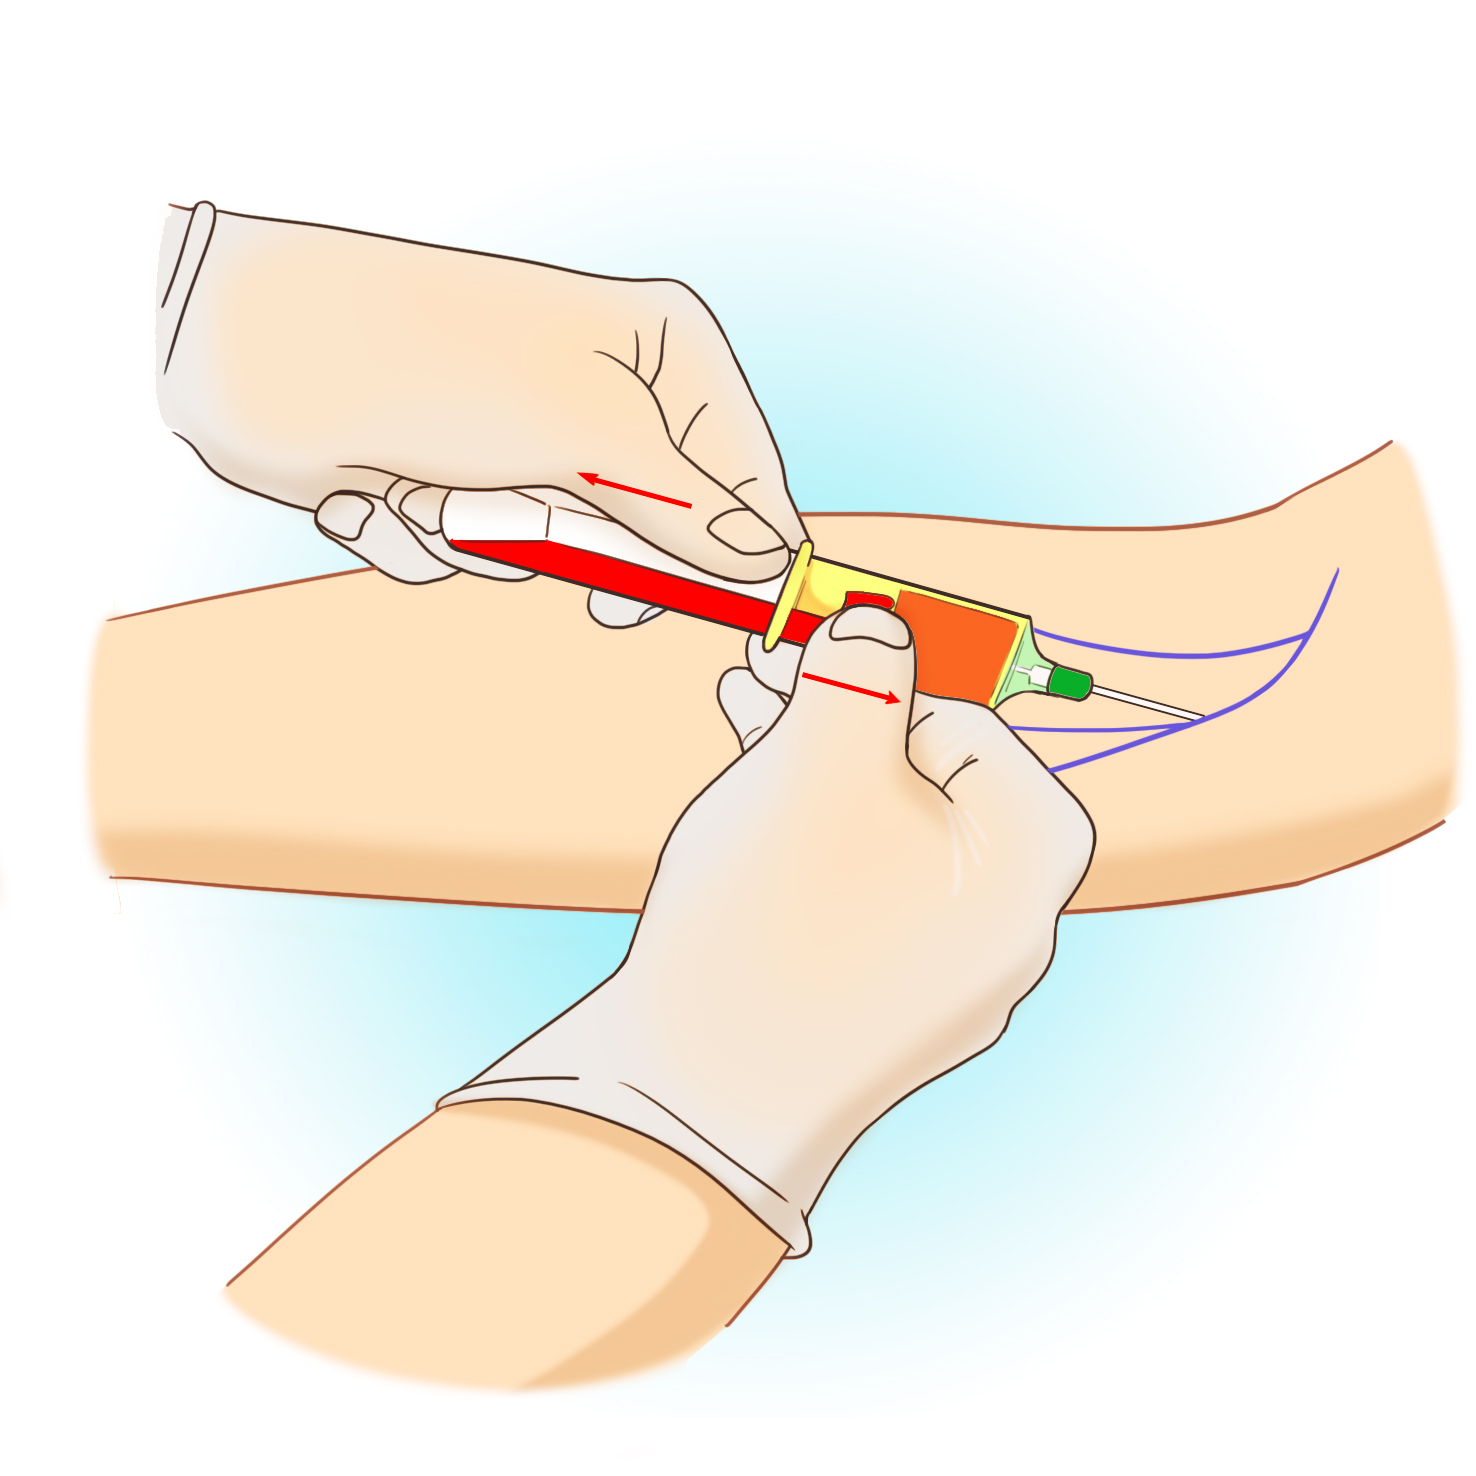

검사 전 준비사항은 없으며, 팔의 정맥에서 혈액을 채취하여 검사를 시행합니다.